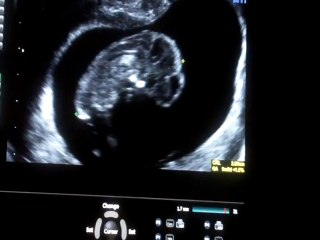

HAFTA HAFTA Gebelik Takibi deneyimli kadın doğum uzmanı Op. Dr. Fatih Esen'in videolu anlatımıyla Bebek.Tv'de: br br br 38 Haftalık Gebelik: br br Deneyimli kadın doğum uzmanı Op. Dr. Fatih Esen anne-baba adaylarına gebeliğin 38. haftasında anne adayı ve bebekte neler yaşandığını anlatıyor, önemli hatırlatma ve tavsiyelerde bulunuyor. br br Bu video Hafta Hafta Gebelik kanalı kapsamında Bebek.Tv tarafından hazırlanmıştır. br br Gebelik-doğum-bebek gelişimi videoları Bebek.Tv'de: br Bebek videoları: br Hamilelikte beslenme: br Kaç haftalık hamileyim, kaç aylık hamileyim? br Hamilelikte öksürük bebeğe zarar verir mi? br br Bebek.